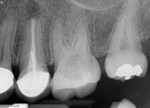

A patient presented with swelling apical to both teeth Nos. 13 and 14 (Figure 1). The dental history revealed that endodontic treatment had recently been performed on both teeth and that a large post had been placed in tooth No. 13. Apical microsurgery was performed on both teeth, and perforating apical lesions were noted on both tooth No. 13 and the mesiobuccal root of tooth No. 14. Under microscopy, a root-end resection and ultrasonic retropreparation were performed and root repair putty (EndoSequence® BC Root Repair Material Putty, Brassler USA) was placed (Figure 2). At a 2-year follow-up appointment, the patient was asymptomatic and healing was noted radiograpically (Figure 3).

Outcomes have improved significantly with the modernization of surgical techniques. Traditional surgery, which used little to no magnification, bur preparation, and amalgam or intermediate restorative material (IRM) retrofills, was associated with markedly unpredictable outcomes. When comparing the outcomes of traditional and modern techniques, one study found that the use of traditional surgical techniques demonstrated success rates of approximately 59% whereas more modern approaches demonstrated success rates of about 94%.6 Modern endodontic surgery incorporates several technological advancements, including CBCT imaging, surgical microscopy, ultrasonic preparation, and bioceramic filling materials. There are immediately visible radiographic differences between traditional (Figure 4) and modern surgical approaches (Figure 5). In the radiograph depicting the traditional surgical approach, note the uneven apical resection on tooth No. 10, the wide retropreparation of the canal space that was performed with a bur, and amalgam fill within the apex (Figure 4). Modern surgical approaches, like those depicted in the radiograph of the treatment of tooth No. 13, facilitate even resection at a minimal bevel and employ retropreparations that better conform to the existing canal spaces (Figure 5). Consequently, the root retrofills appear as an extension of the existing root canal fillings.